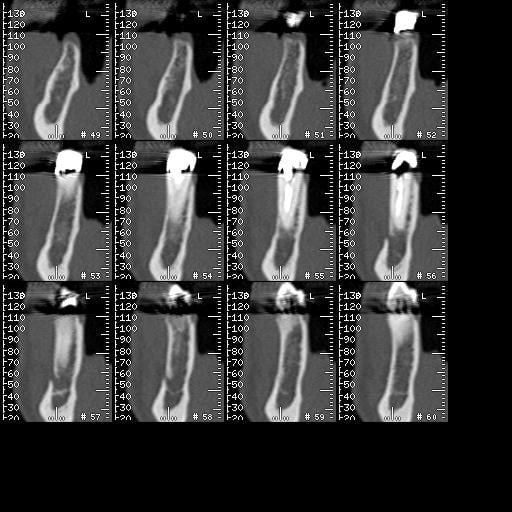

pour répondre à ta question : depuis 1994 , oui d ailleurs dans un des cas présentés tu as une radio après 10 ans :-)! (46 47 )

"Exp dans ce cas 4,5/10mm en 36 dans un site d'extraction récent placé en 12mm soit deux millimètres plus profondément"

Formidable , tu as des scans à passer , merci ?

Maintenant concernant la demande de scans : je poste ce cas, une patiente vient me voir avec son scan car elle a consulté d'autres "spécialistes" et on lui refuse la pose d'implant secteur 4 où alors avec greffe préalable..Ca se discute..pas de temps à perdre je sais faire autrement..

Avec la chir trans gingivale technique MIMI ( Oui..un post sur la technique bientôt ..) j'ai pu placer deux 3,5/8mm..aurai je eu le meme résultat avec un lambeau..j'en doute..Les couronnes sont en titane. Recul clinique 2 ans ras. Simple efficace rapide moins onéreux satisfaisant pour le praticien et la patiente..